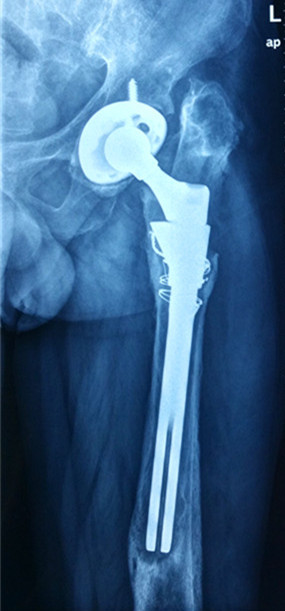

初次置换

患者宋先生,60岁,20年前在施工时不慎受伤,导致左髋部股骨颈骨折。在当地医院接受了“左侧人工股骨头置换”手术。7年前,患者再次受伤,导致左侧人工髋关节“假体周围骨折”。接受了“左人工髋关节二次翻修术”。1年前患者出现了左侧髋部慢性疼痛,半年前疼痛加重来我院就诊,X线检查提示“左人工髋关节假体松动下沉,周围骨质大片缺损”,诊断“人工髋关节术后感染”。